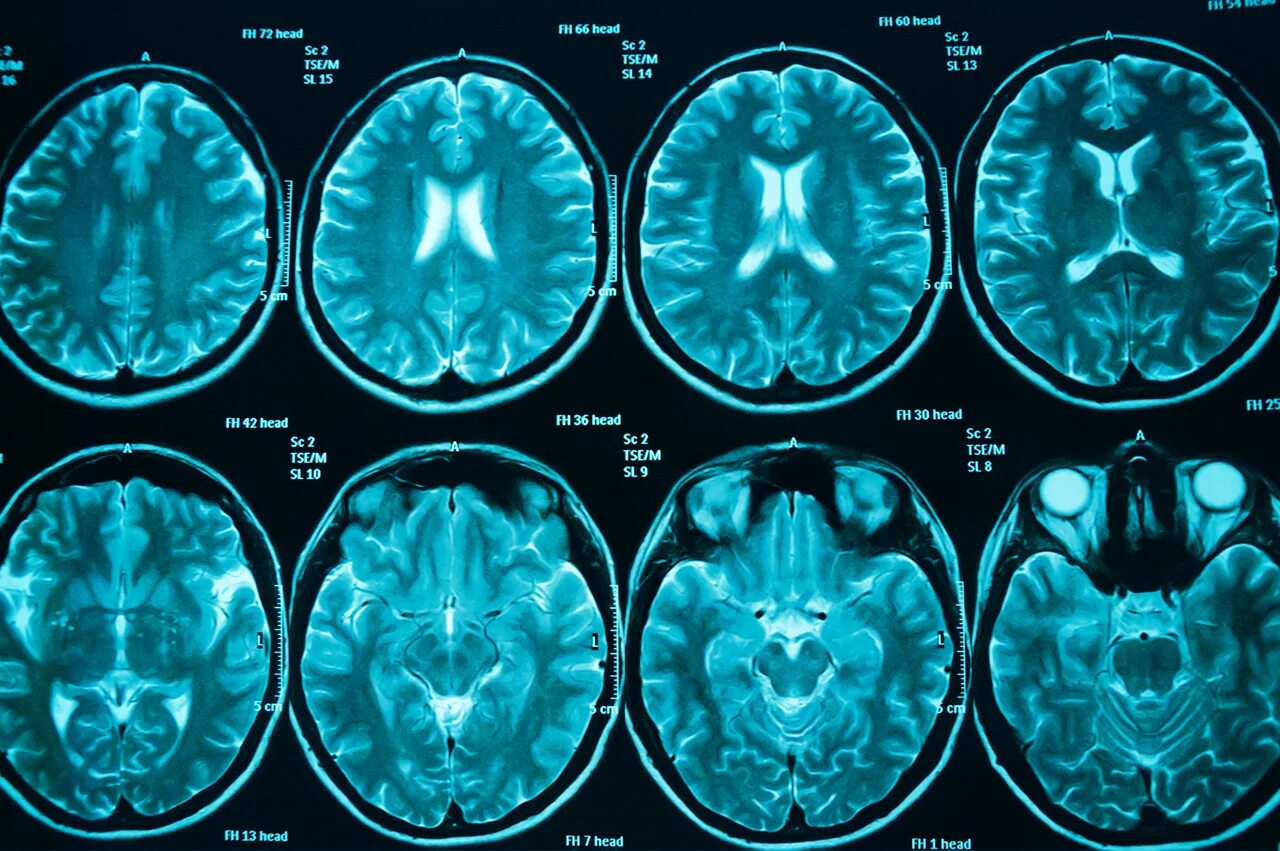

После мрт головного мозга